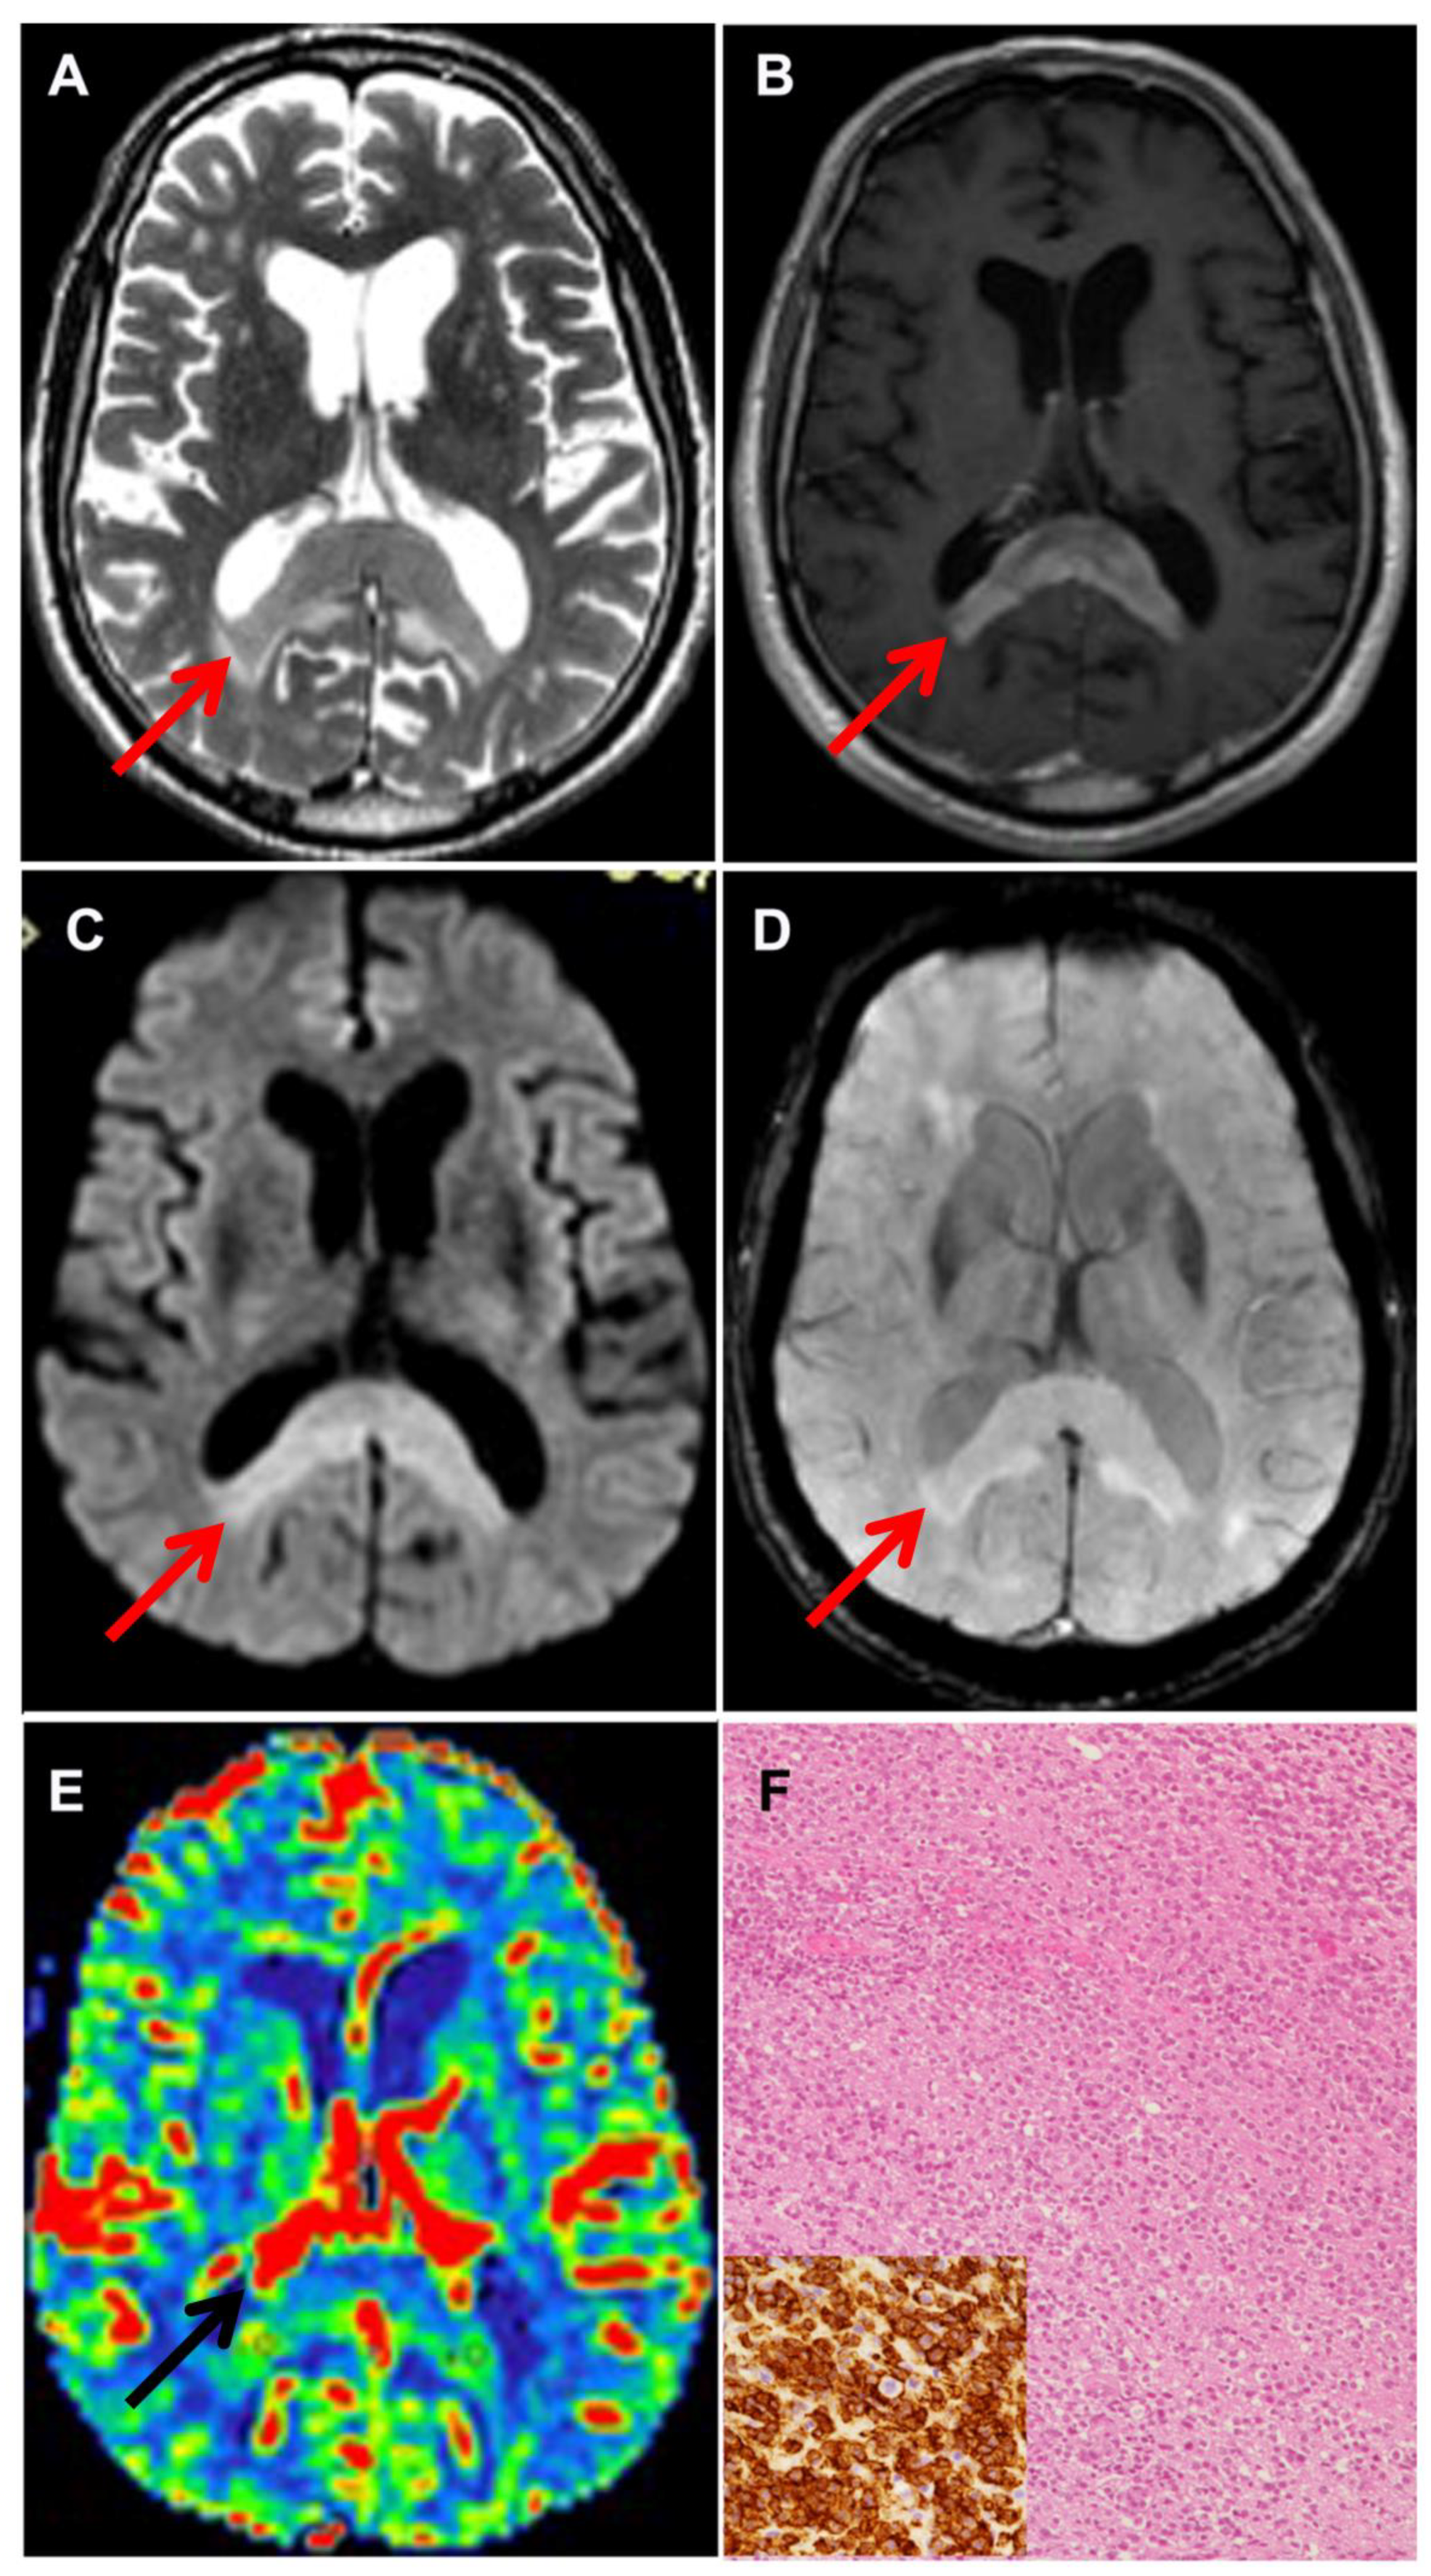

2.2. Radiological Evaluation

3.4. Follow-Up of Biopsy Patients